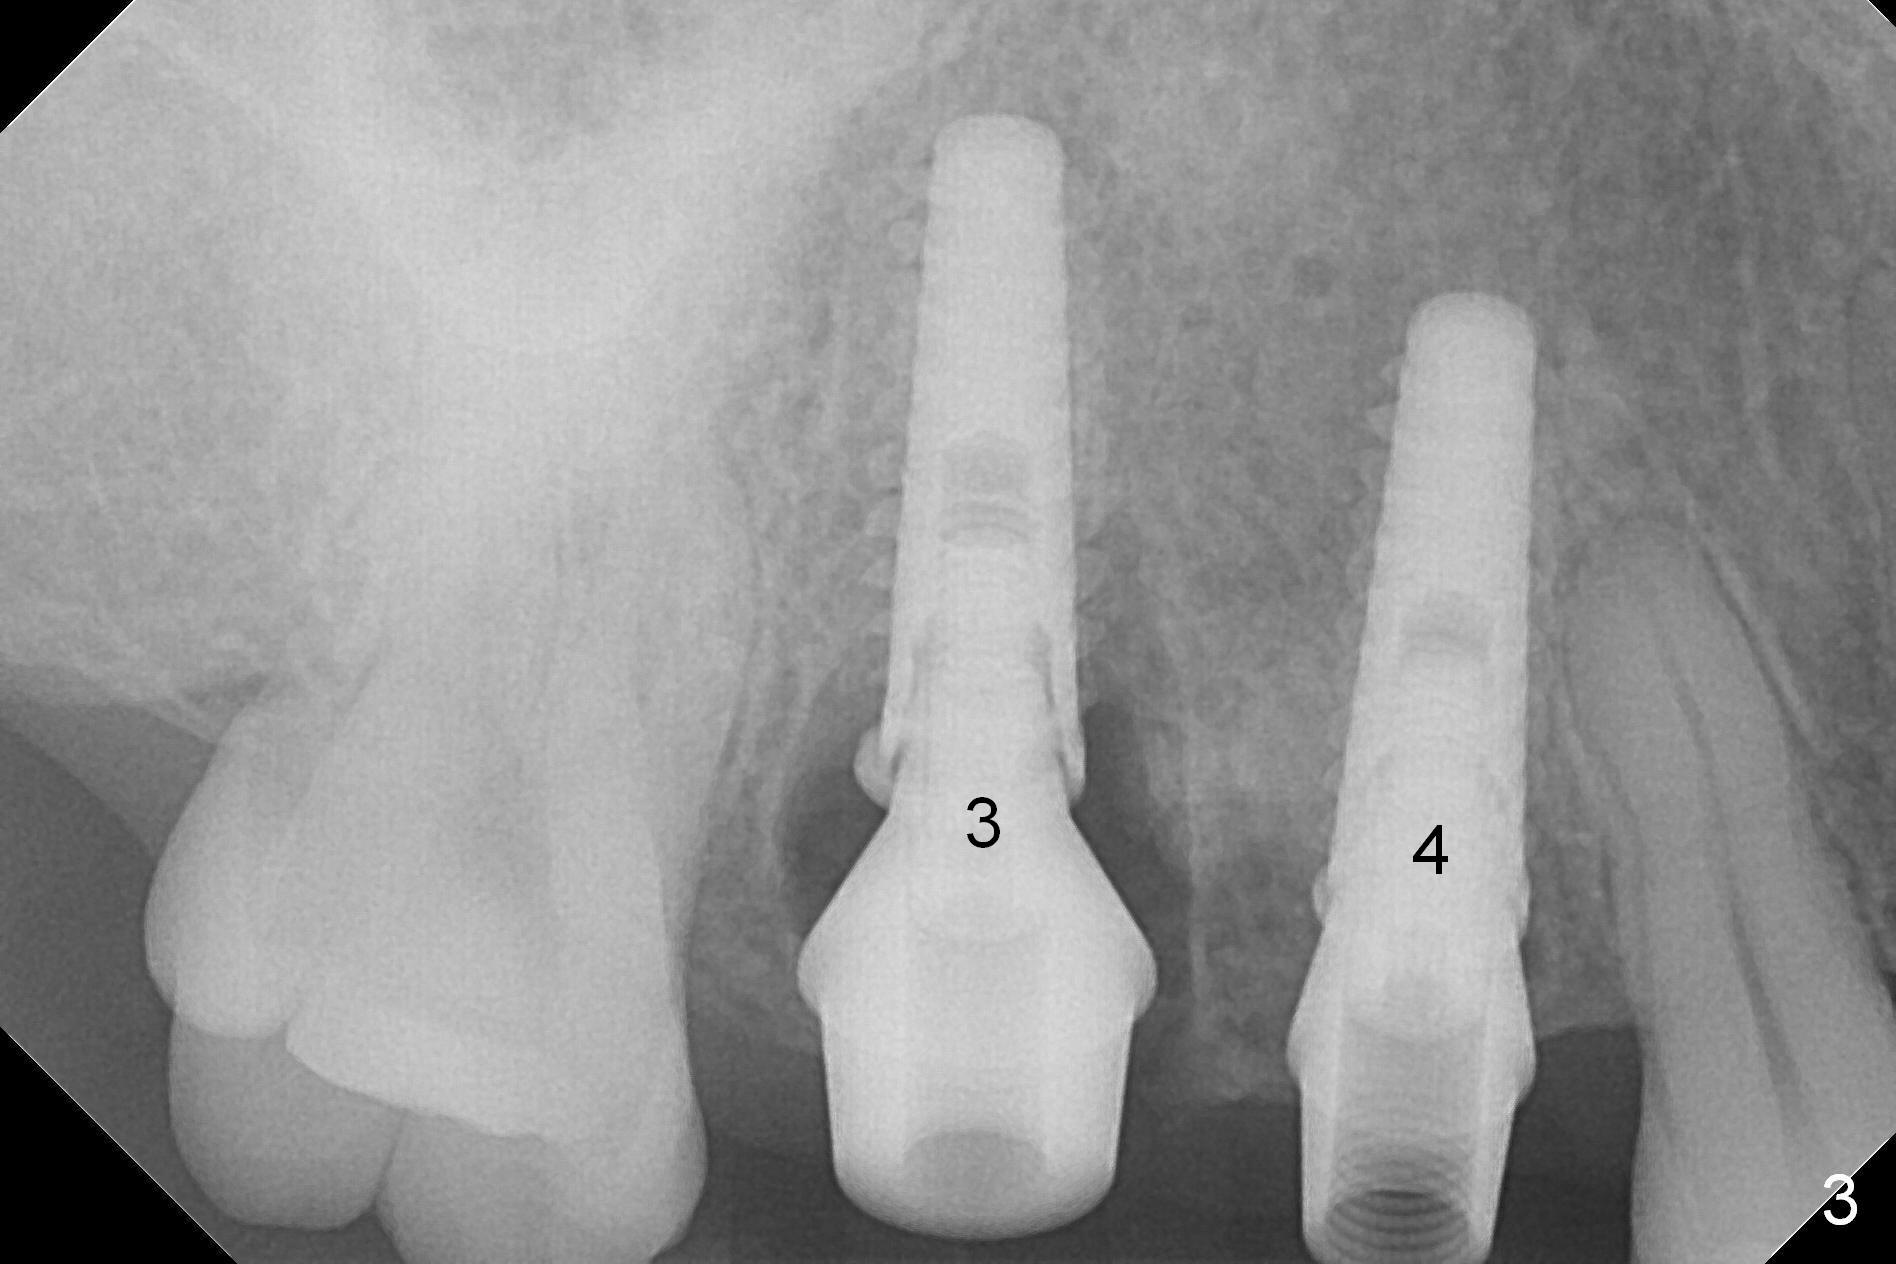

After extraction, osteotomy is established in the septum of #3 and the mesial slope of the shallow socket of #4 (Fig.2 red dashed line) for 11 and 13 mm deep, respectively. Since the septum is sloped palatally, a series of Magic Drills (MD) are used. A single large MD may wobble in the slope. By the time MD 3.8 mm is used, there is perforation palatally. The insertion torque of 4.5x13 mm IBS implant is less than 30 Ncm (Fig.3). In retrospectively, the osteotomy should have been initiated more buccally or deeper, since there is fair amount of clearance from the sinus floor (Fig.5 ^). The implant at #9 is 3.8x16 mm.